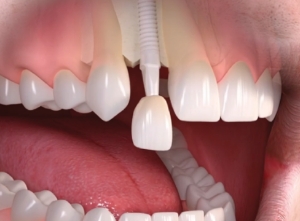

ایمپلنت دیجیتال در پاوه: راهنمای کامل برای داشتن لبخندی سالم

داشتن دندانهای سالم و زیبا یکی از مهمترین عواملی است که بر اعتماد به نفس و کیفیت زندگی افراد تأثیر میگذارد. امروزه روشهای سنتی ایمپلنت به دلیل طولانی بودن روند درمان و دردناک بودن آن، دیگر اولین گزینه بیماران نیست. ایمپلنت دیجیتال در پاوه به عنوان یکی از پیشرفتهترین روشها،